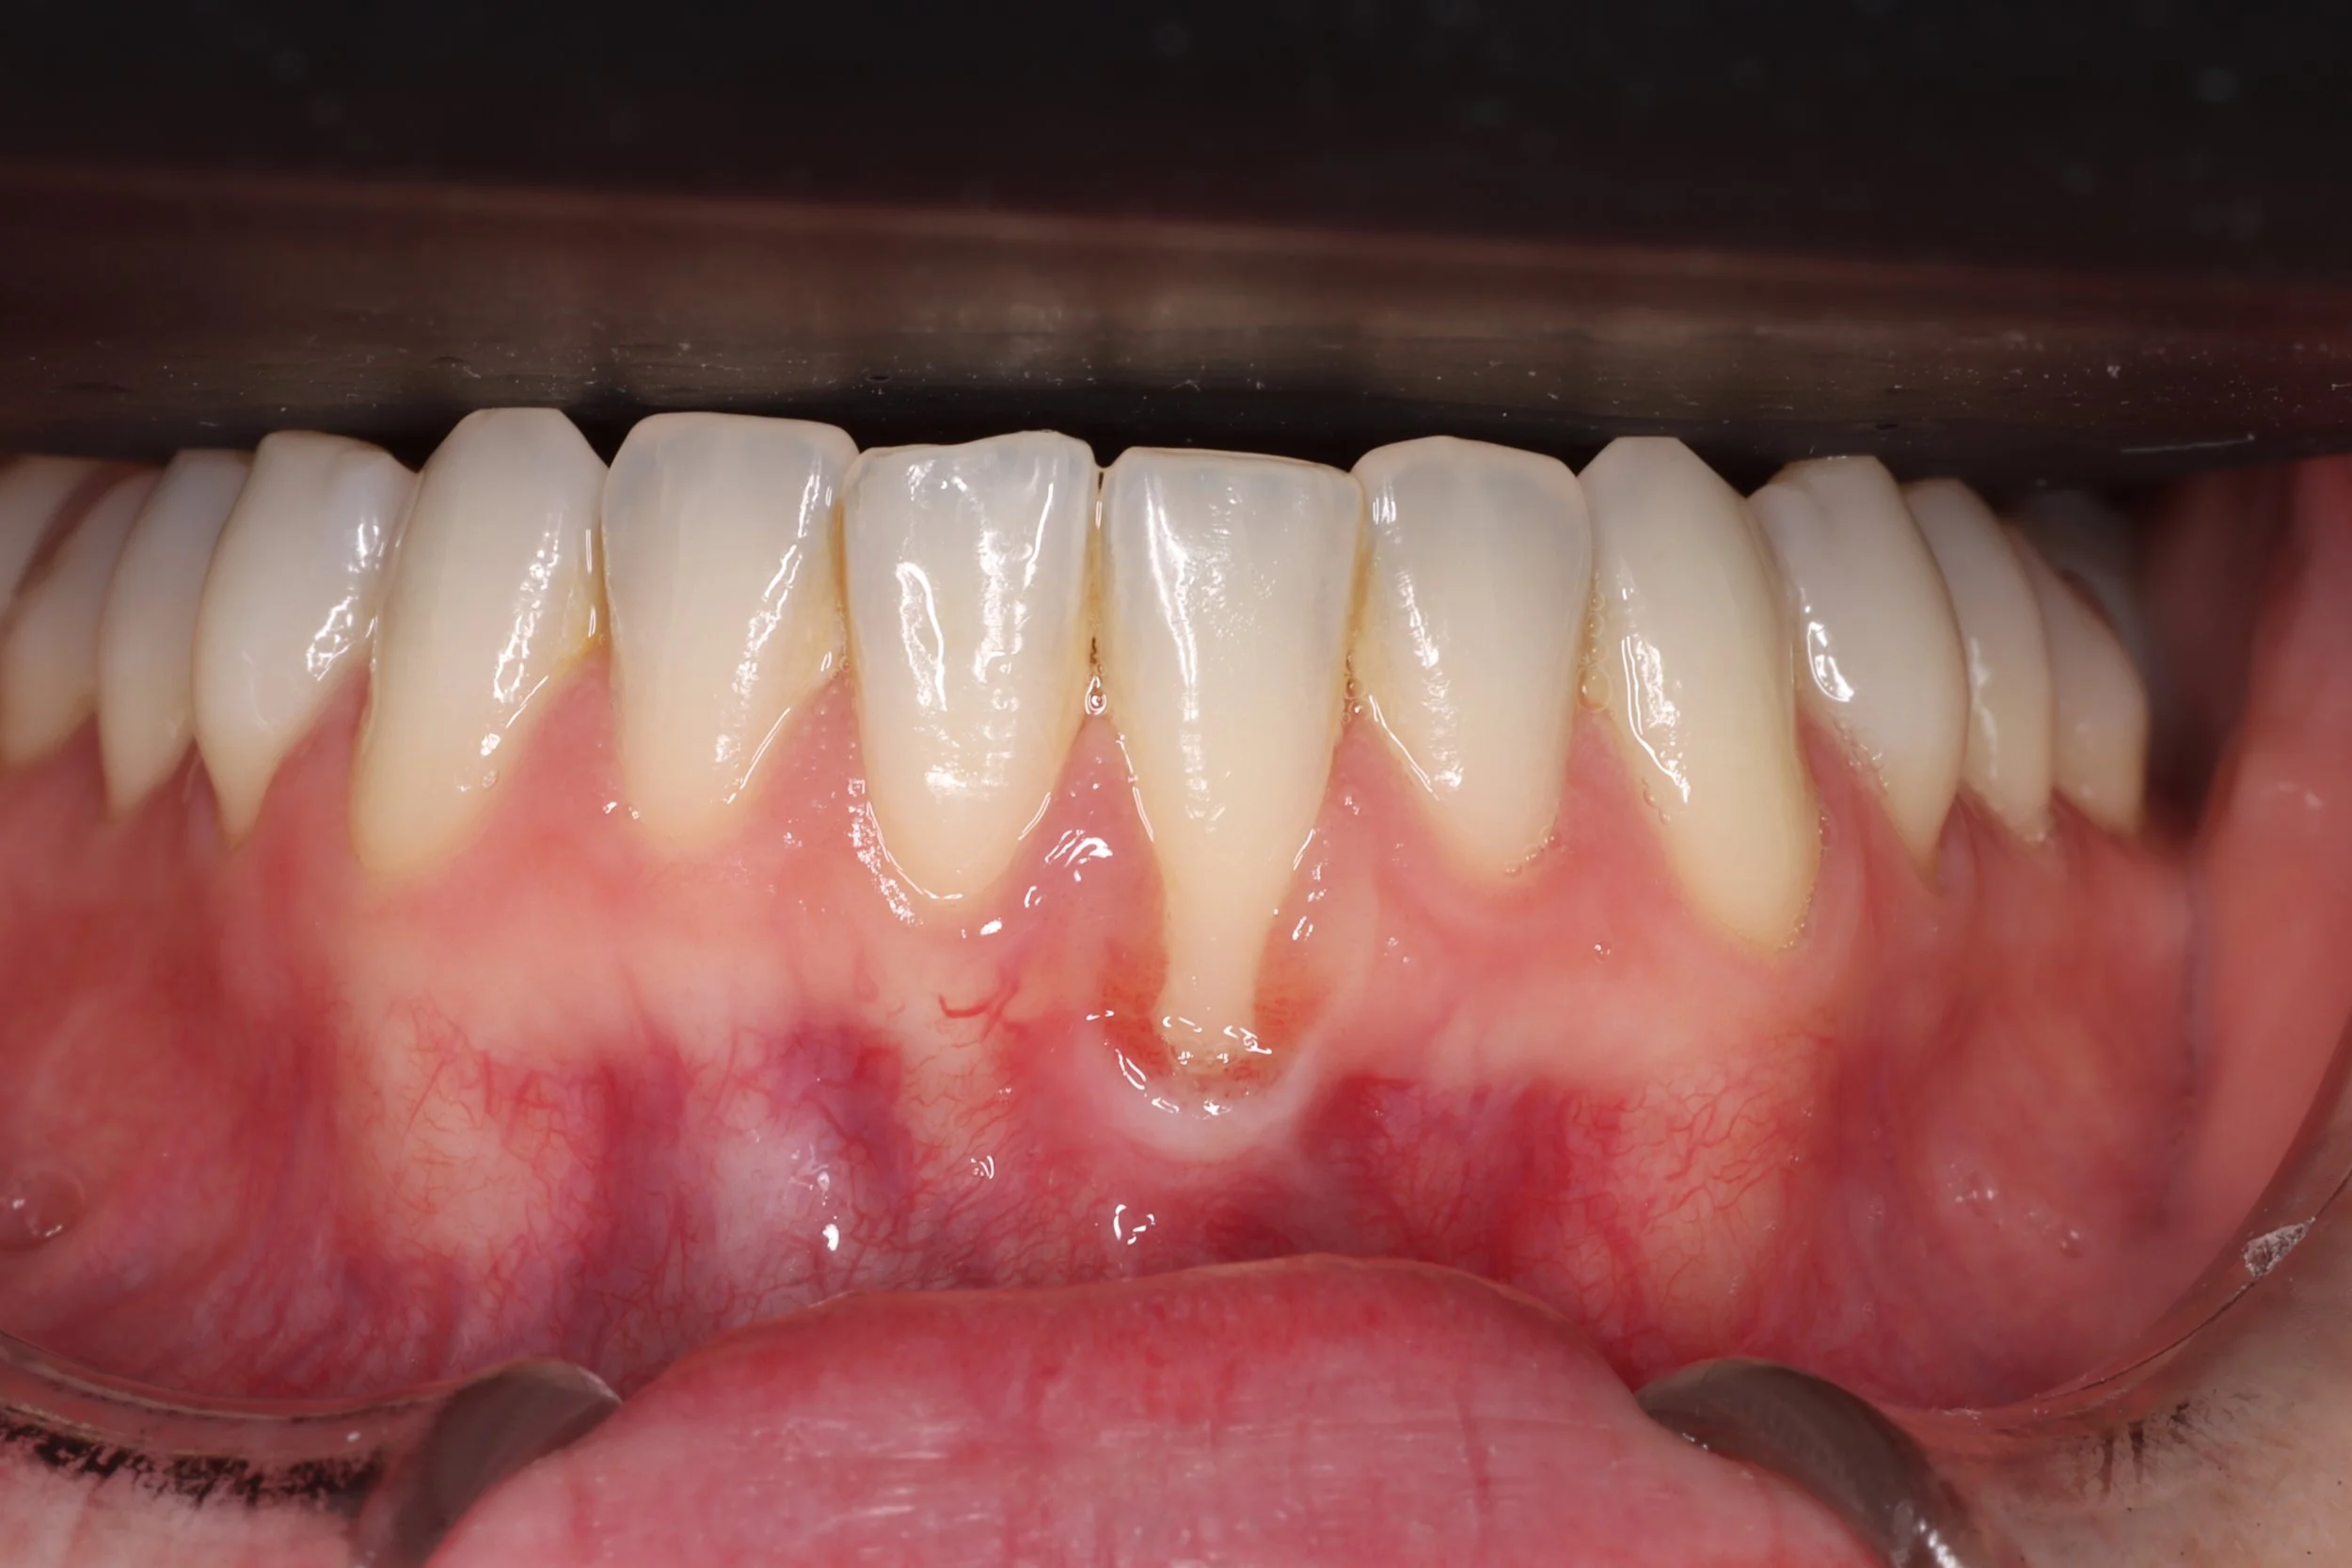

A nuestra clínica acuden pacientes con problemas de encías de sangrado, inflamación, sensibilidad, o retracción de encías que son tratados de forma individual, enseñándoles además como mantener las encías y mejorarlas, estableciendo un programa de citas de mantenimiento periódico.

• Injerto de encía